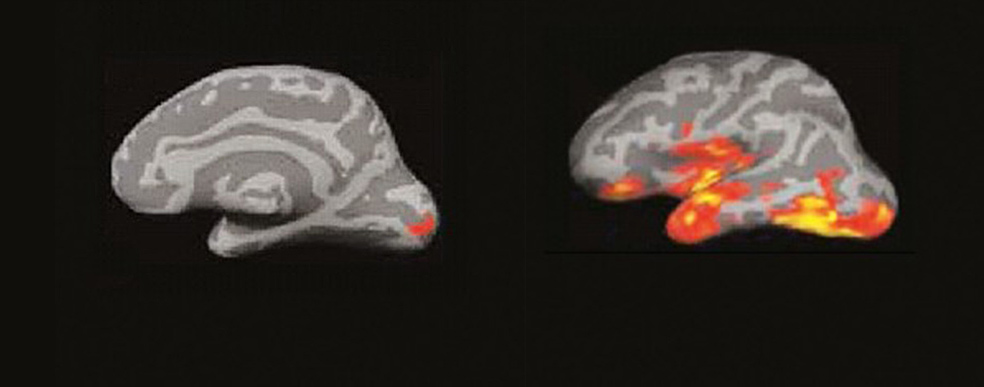

El cerebro del lector: un incendio de ideas

La imagen por resonancia magnética del cerebro de alguien que lee muestra algo parecido a un incendio forestal en un día de viento. Las pavesas vuelan y prenden nuevos conatos en diferentes zonas…